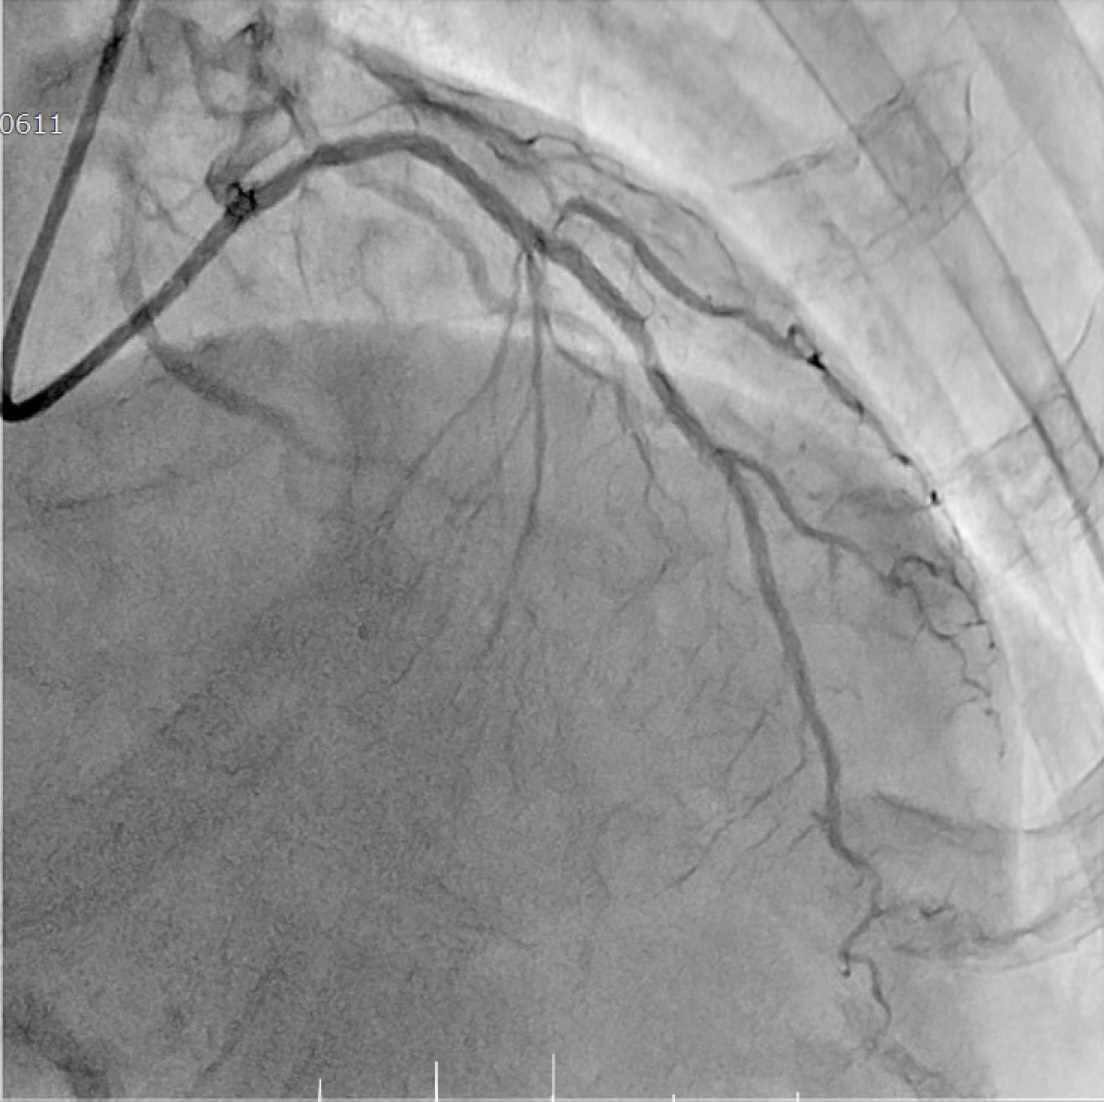

Coronary angiography revealed tandem lesions in the left anterior descending artery and a severe stenosis in the circumflex artery. The proximal left anterior descending artery was a severe bifurcation lesion (Fig 2 and 3).